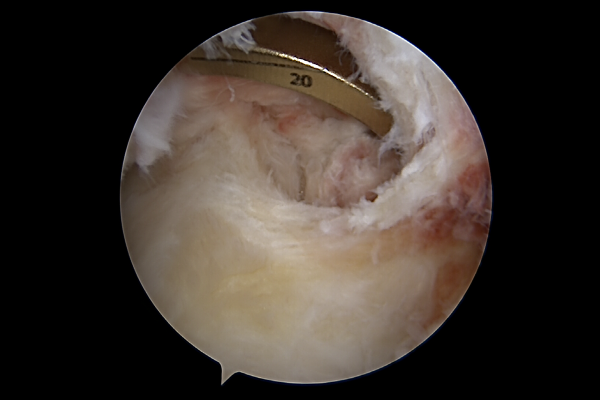

무릎의 앞쪽에서 확인했을 때 재건될 후방십자인대 위치에 가이드 와이어가 있는 것을 확인하고서

가이드 와이어에 실을 연결하여 재건한 인대를 올려줍니다.

최종적으로 잘 재건된 십자인대를 확인할 수 있습니다.